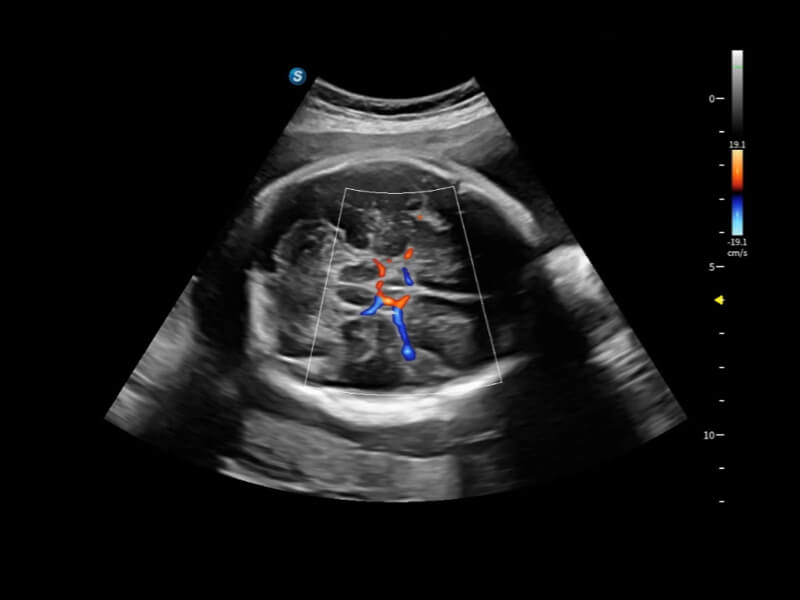

Fein abgestimmte hämodynamische Lösung

Eine Vielzahl hämodynamischer Diagnosetechniken ermöglicht eine effektive Blutflusssignaldetektion in verschiedenen Szenarien.

• FHR

FHR ermöglicht die Beobachtung der mikrovaskulären Struktur in Organen mit erhöhter Empfindlichkeit und verbesserter Auflösung, um die Präzision bei der Darstellung des tatsächlichen Zustands der Blutzirkulation sicherzustellen.

• Bright Flow

Bright Flow bietet eine 3D-ähnliche Farb-Doppler-Flow-Visualisierung ohne den Einsatz eines Volumenwandlers, wodurch die Grenzdefinition der Gefäßwände verstärkt wird.

• Micro F

Micro F unterscheidet subtile Blutflusssignale effizient von überlagerter Gewebebewegung und ermöglicht eine erhöhte Empfindlichkeit sowie räumliche Auflösung in der hämodynamischen Darstellung.